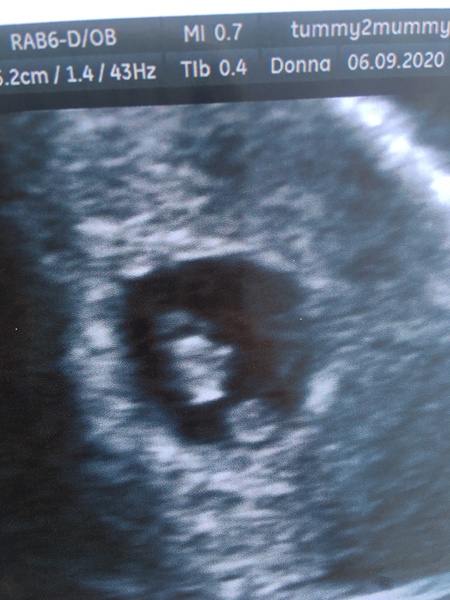

Scan went really well!! Baby has caught right up. It’s grown 11 days in the past 9! I’m now measuring 7+3 and I think I’m roughly 7+4 today so baby is bigger than the last one now. She could see the arm buds developing ❤️ Really relieved and happy. I’ve booked in again for sat 19th lol. X

Ahhh congrats, @Pugprincess! 🥰 Looks like a little jelly baby 😍